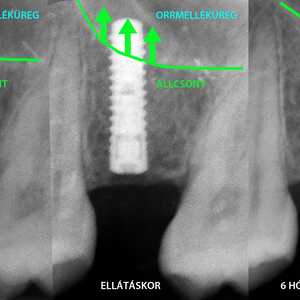

Lépésről lépésre: egy komplex fogimplantátum és csontpótlás története Kecskeméten. Nézze meg, hogyan spóroltunk hónapokat páciensünknek 3D tervezéssel!

Egy komplex fogpótlás története – az alapoktól az új mosolyig Nagy örömmel számolunk be egy különleges, komplex fogimplantátum-csontpótlás-fogpótlás ellátásunkról, amit nemrég fejeztünk be. Büszkék vagyunk…